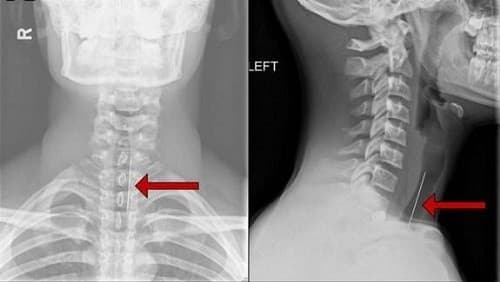

Chụp X quang vùng cổ là một cách giúp chẩn đoán chứng đau cơ ở cổ

– Chụp X quang: X quang có thể tiết lộ các khu vực ở cổ, nơi dây thần kinh hay tủy sống có thể bị chèn ép bởi xương hoặc lồi đĩa. Nhưng nhiều người, đặc biệt là những người trên 60 tuổi, có những phát hiện này và không đau cổ.